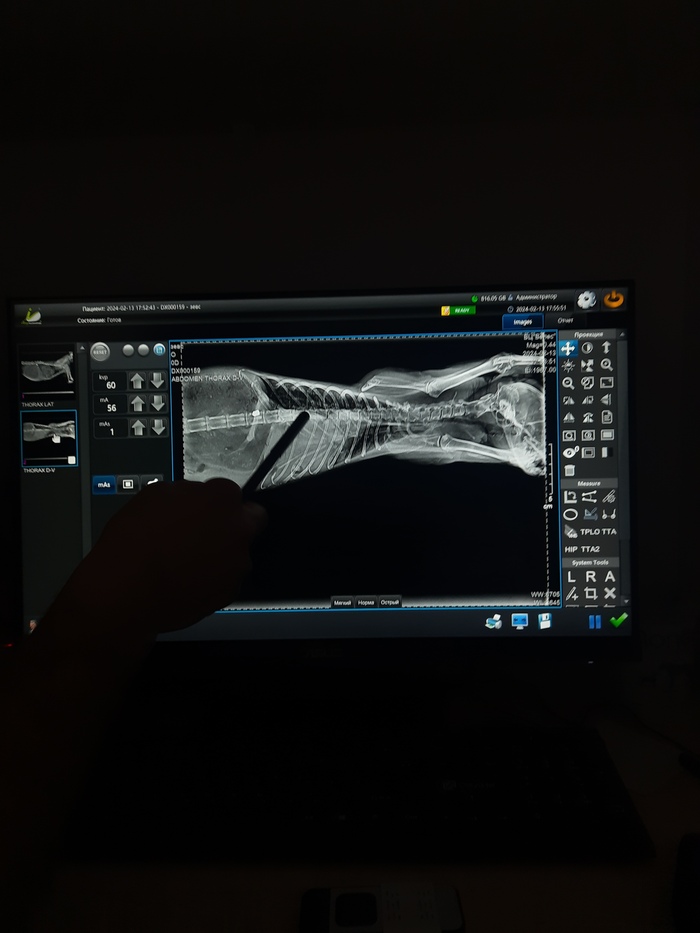

Поехали вчера после работы с Зевсом в ветклинику.

Дела очень, очень грустные у кота...

Пока ехали коту стало ещё хуже, он начал тяжело дышать, открыл рот, хватал воздух, шипел. Я подумала что всё, такие конвульсии мы уже видели, к сожалению....

Мы успели. Спасибо просто огромнейшее за оперативность врачам и ассистентам ветклиники Велес. Они мгновенно взяли кота, сделали узи, поставили катетер, сделали рентген и посадили в бокс на кислород.

У кота застрявшая пуля под позвоночником. Свежая она или нет, пока непонятно.

У кота пробито и сдулось одно лёгкое, с правой стороны, разрыв диафрагмы и выпад кишечника в грудную полость.

Связанно это с пулей или нет, тоже пока непонятно.

По анализам кот как-будто месяц не ел...

Врач не исключает и абсцесса внутри, тк лейкоциты за 40тыщ улетели...

По задним конечностям претензий нет, рентген показал все кости целы!